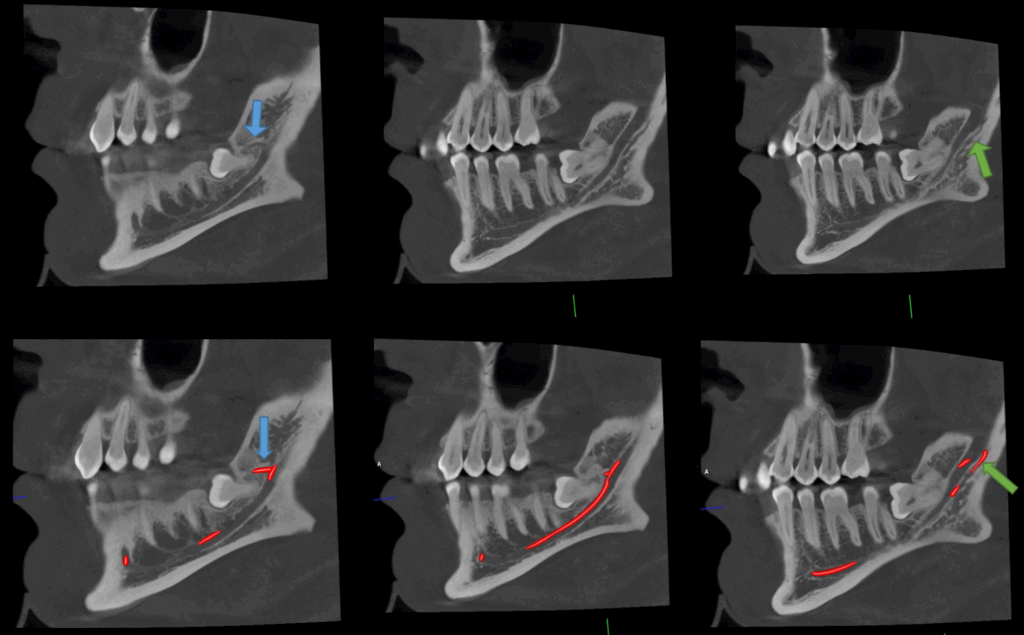

A la evaluación de la tomografía computarizada y al momento de localizar el recorrido del conducto dentario inferior se evidencia la presencia de dos conductos accesorios, el primero y mas cefálico se orienta hacia la porción coronaria de la pieza 48 y el segundo y más caudal se observa de tipo recurrente y no se encuentra en relación con ninguna pieza dentaria.

CORTES TANGENCIALES

caso 344 - CORTES TANGENCIALES IDM